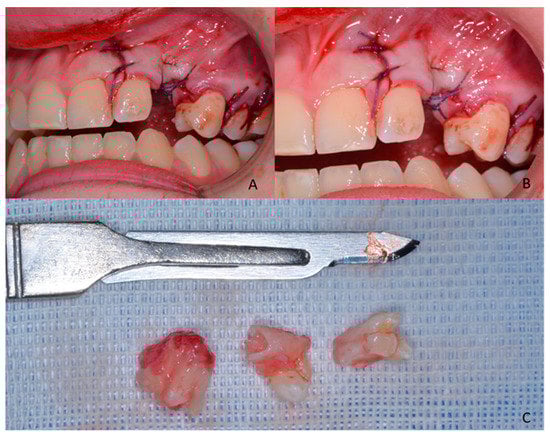

1.1. Case Number 1